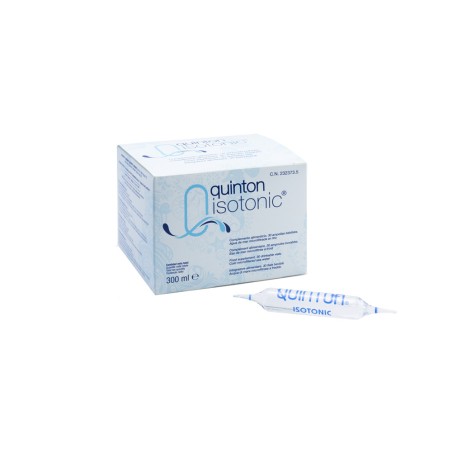

Quinton Compléments Alimentaires

22,90 €28,90 €Prix de base-6,00 € éteintPrix

Quinton Compléments Alimentaires

22,90 €28,90 €Prix de base-6,00 € éteintPrix

Quinton Compléments Alimentaires

Eau de mer océanique isotonique , microfiltrée à froid Contribue à une digestion normale (chlorure). Complément alimentaire Vente uniquement en France métropolitaine, DOM TOM et Belgique

22,90 €28,90 €Prix de base-6,00 € éteintPrix